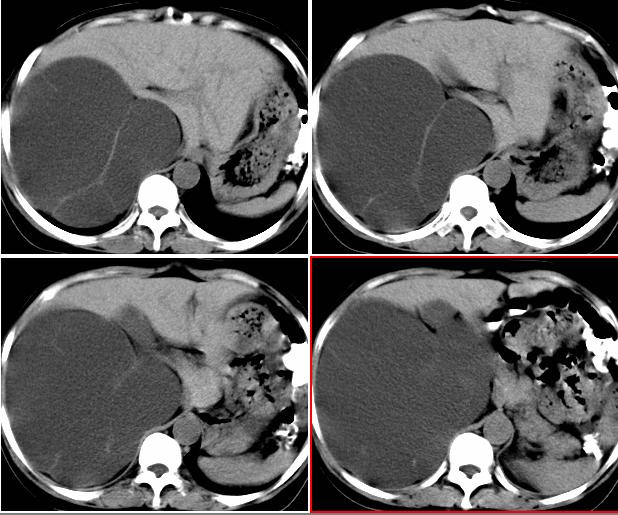

右侧后腹膜巨大囊性肿块影阴,边缘清晰,内见膜状分隔,均匀水样密度,右肾影阴消失,囊块所到区域脏器受挤移位,右侧输尿管扩张,应该考虑:右肾重读积水,巨大肾囊肿不除外。引发肾性高血压。

腹部巨大囊性占位,膨胀性生长,边界光整,囊内容物为水样密度,其内可见多发分隔,纵观所有层面,正常右肾未见,考虑为来源于右肾的巨大多房性肾囊肿(多房性囊性肾瘤)可能性大。

腹部巨大囊性占位,膨胀性生长,边界光整,囊内容物为水样密度,其内可见多发分隔,右恻输尿管全程扩张,纵观所有层面,正常右肾未见,考虑为来源于右肾的巨大多房性肾囊肿可能性大。

反推一下:1.那么重的积水,引起积水的原因大部分是右侧输尿管有梗阻,排出受阻。右侧输尿管应该也是重度扩张才对。2.如果是肾积水,而且是右侧输尿管问题引起,那么病人肯定有相应的临床症状:比如输尿管结石引起的血尿、剧痛等症状,至少也会急性发作病史。另,本例显然不需要考虑输尿管癌,膀胱也挺好,更没有无痛性血尿病史。病人8年多没有其他的不舒服,只是腹部日渐膨隆,临床症状显然不支持。3.如果是重度肾积水的话,应该可以看到被压缩的肾皮质,即使很菲薄也多少会有显示的。

右肾明显扩大,皮质菲薄,间隔细,右输尿管全程扩张,右肾重度积水,原因应重点查输尿管膀胱接合处。

右侧巨大囊状无功能肾,输尿管积水.右侧积水肾旁囊性病灶应该是左侧卵巢浆液性囊腺瘤.